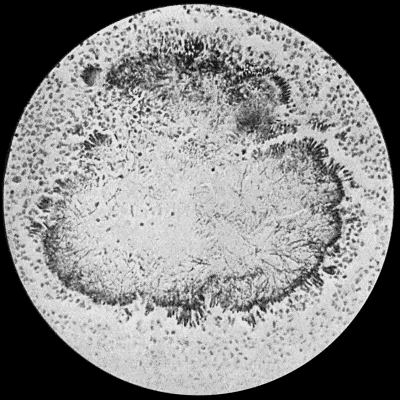

Fig. 2.—Staphylococcus aureus in Pus from case of Osteomyelitis. × 1000 diam. Gram's stain.

Staphylococcus Aureus.—This is the commonest organism found in localised inflammatory and suppurative conditions. It varies greatly in its virulence, and is found in such widely different conditions as skin pustules, boils, carbuncles, and some acute inflammations of bone. As seen by the microscope it occurs in grape-like clusters, fission of the individual cells taking place irregularly (Fig. 2). When grown in artificial media, the colonies assume an orange-yellow colour—hence the name aureus. It is of high vitality and resists more prolonged exposure to high temperatures than most non-sporing bacteria. It is capable of lying latent in the tissues for long periods, for example, in the marrow of long bones, and of again becoming active and causing a fresh outbreak of suppuration. This organism is widely distributed: it is found on the skin, in the mouth, and in other situations in the body, and as it is present in the dust of the air and on all objects upon which dust has settled, it is a continual source of infection unless means are taken to exclude it from wounds.